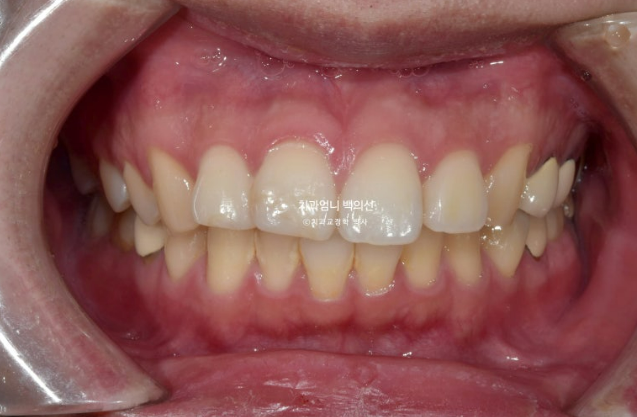

24.11

앞니 사이 틈은 없어졌고 중심선은 정확히 맞습니다.

교합도 퍼펙트 합니다.

입안 사진만 보면 치료를 마무리해도 됩니다.

2022.12~2025.05

앞니 돌출의 개선과 적절한 앞니 각도

두번째 재제작으로 교합평면이 수평을 되찾았습니다.

뻗치지도 옥니도 아닌 적절한 앞니 각도

비로소 입이 편하게 다물어 집니다.